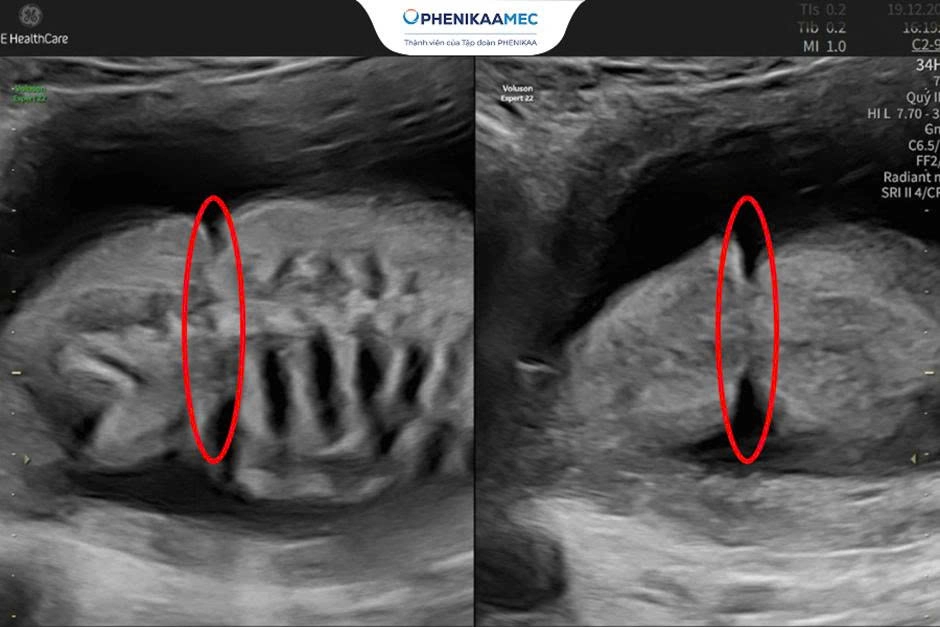

Hình ảnh dải xơ buồng ối gây quấn thắt ngang bụng thai nhi

Hình ảnh siêu âm cho thấy rõ rệt dải xơ buồng ối thắt ngang bụng thai nhi